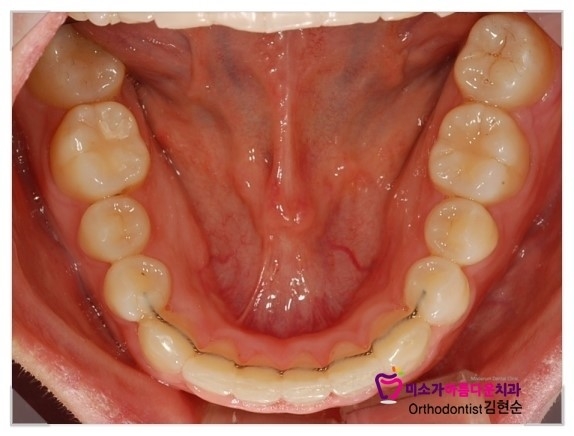

그리고 유지장치는 얇은 철사를 붙여드렸는데

치과에서 교정이 거의 끝난 분들에게 알려드리는 주의사항은

교정이 끝나면 교정기를 빼고 너무 신나서 유지장치를 잊어버리시는 분들이 많은데

치아는 교정이 끝났어도 원래 위치로 돌아가려고 하기 때문에

한동안(교정기간정도)은 유지장치를 꼭 유념해주시고

유지장치를 꾸준히 끼고 다니시다가 천천히 끼는 시간을 줄여주시는 편이 좋습니다.

치아 안쪽에 철사처럼 보이는 것은 교정이 끝나고 붙이는 교정 유지장치입니다.

교정후 교정유지장치를 하지 않으면 치아가 원상태로 돌아가기때문에 교정한 기간만큰 꼭 해주어야 합니다.